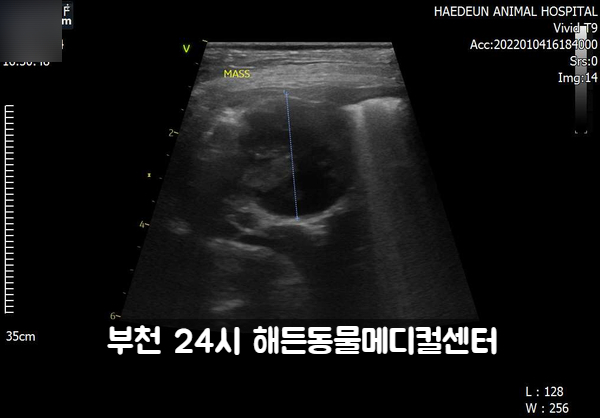

초음파 검사를 하겠습니다.

허든 초음파는 미국 GE사의 최신 vivid-T9 초음파를 사용합니다.영상전공의가 직접 검사라고 판독합니다.

초음파상에 자궁촉농증이 확인됩니다.

소장 종양이 의심됩니다.